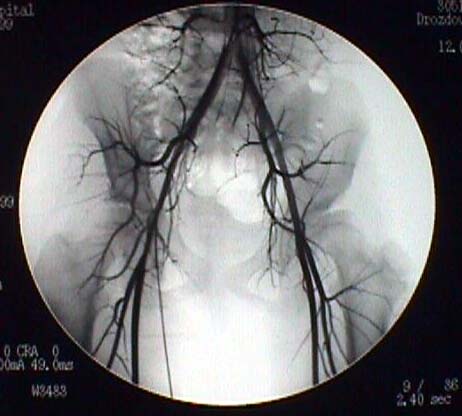

При обследовании периферических сосудов необходимо владеть известными методами ангиографии, знать их преимущества и отрицательные стороны, чтобы выбрать оптимальный вариант способа. Наилучшие результаты достигаются при селективных способах.  С помощью ангиографии были выявлены        следующие изменения при врожденном вывихе бедра: сужение просвета магистральных артерий, уменьшение числа и длины мелких ветвей, отсутствие анастомозов, что приводит к заметному снижению плотности сосудистого рисунка. При одностороннем процессе эти симптомы особенно заметны.      Уменьшение диаметра подвздошных и бедренных сосудов, их ветвей на пораженной стороне приводит к заметному снижению емкости и пропускной способности сосудистого русла и влечет за собой хроническую недостаточность кровоснабжения данного сегмента.

angio.jpg (32219 bytes)